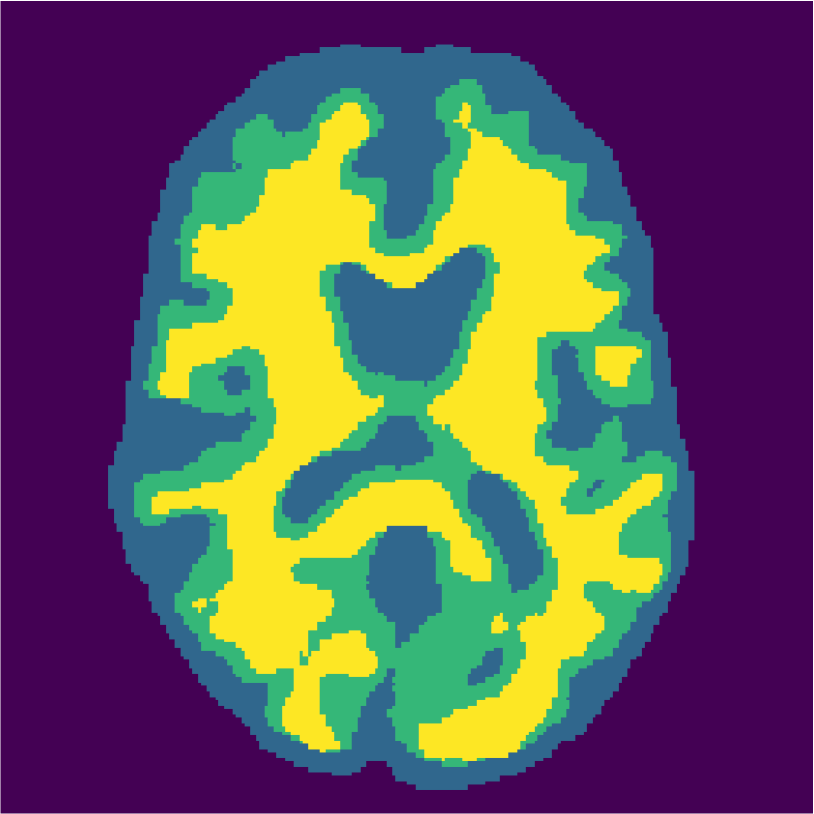

Examples of the segmentation results on one of the target test images are shown in Figure 8 for experiment 2.1, Figure 9 for experiment 2.2, and Figure 10 for experiment 2.3. Examples are shown after using 1 target patch per tissue for training, and after using 100 target patches per tissue for training. The results show that only the mrai-net classifier is able to predict a segmentation that approaches the ground truth with only 1 target patch per tissue for training (error for experiment 2.1 = 0.269, experiment 2.2 = 0.403, experiment 2.3 = 0.320), while the source and target classifiers cannot (source error for experiment 2.1 = 0.667, experiment 2.2 = 0.653, experiment 2.3 = 0.435; target error for experiment 2.1: 0.591, experiment 2.2: 0.614, experiment 2.3 = 0.596). After using 100 patches the source and target classifiers can predict a gross segmentation of WM, GM and CSF (source error for experiment 2.1 = 0.213, experiment 2.2 = 0.384, experiment 2.3 = 0.363; target error for experiment 2.1: 0.205, experiment 2.2: 0.368, experiment 2.3 = 0.368), but the mrai-net classifier prediction shows more details and a lower tissue classification error (error for experiment 2.1 = 0.111, experiment 2.2 = 0.276, experiment 2.3 = 0.284).